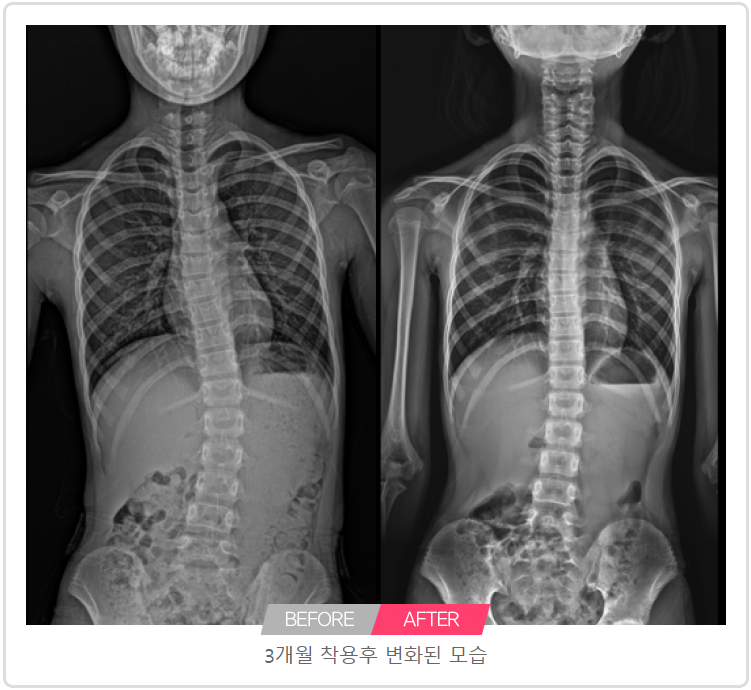

3개월 착용후 교정된 모습

JAMSIL SAENAE STATION ORTHOPEDIC CLINIC